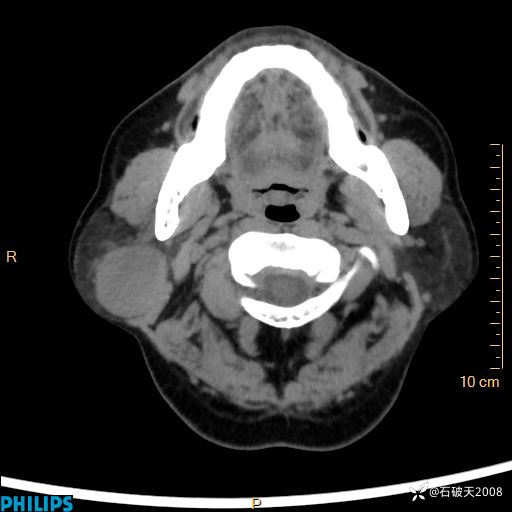

静脉期